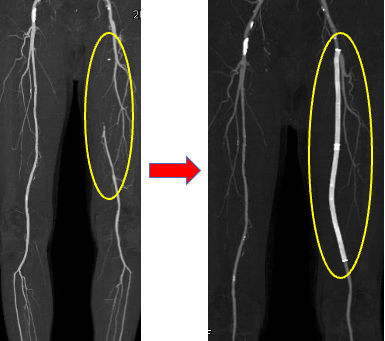

②の左浅大腿動脈閉塞の方は、駅から当院まで徒歩で来られる際に休み休みでないと来ることができないという間欠性跛行という症状を訴えられ、治療に至った患者さまです。

②左浅大腿動脈閉塞